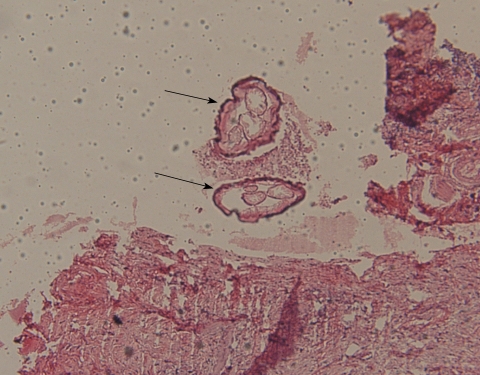

Histological examinations revealed multiple sections of a nematode with central eosinophilic and neutrophilic infiltration surrounded by granulomatous and fibrous tissues (Fig. 1). Morphologic evaluation showed a nematode with multilayer thick cuticles, indistinct intestinal cells, numerous external ridges, distinct dorsal and ventral fields of divided coelomyarian somatic musculature, 2 internal longitudinal ridges with broad lateral chords, heavy musculature, and didelphic uterine tubes with a small extra branch empty of microflariae. These findings suggested it to be a mature female worm of Dirofilaria repens (Fig. 2). Treatment with topical steroids was commenced.

Definite diagnosis requires surgical removal and pathological examination of the specimen. Diagnosis is made through histological and morphological evaluation of the worm. The presence of thick laminated cuticles, large muscle cells, and wide lateral chords is diagnostic for this parasite. Identification of the species depends on macroscopic examination of the mature worm. In cases of deep tissue involvement where only histopathologic specimens are available, studying the size and features of the body wall, i.e., cuticle thickness and structure, ridges, number of lateral chords, and muscle cell type can help the differential diagnosis of the species. An accurate diagnosis can also be made through PCR-based DNA analysis especially when conventional morphologic assessment is not possible due to poor worm conservation [1,12].